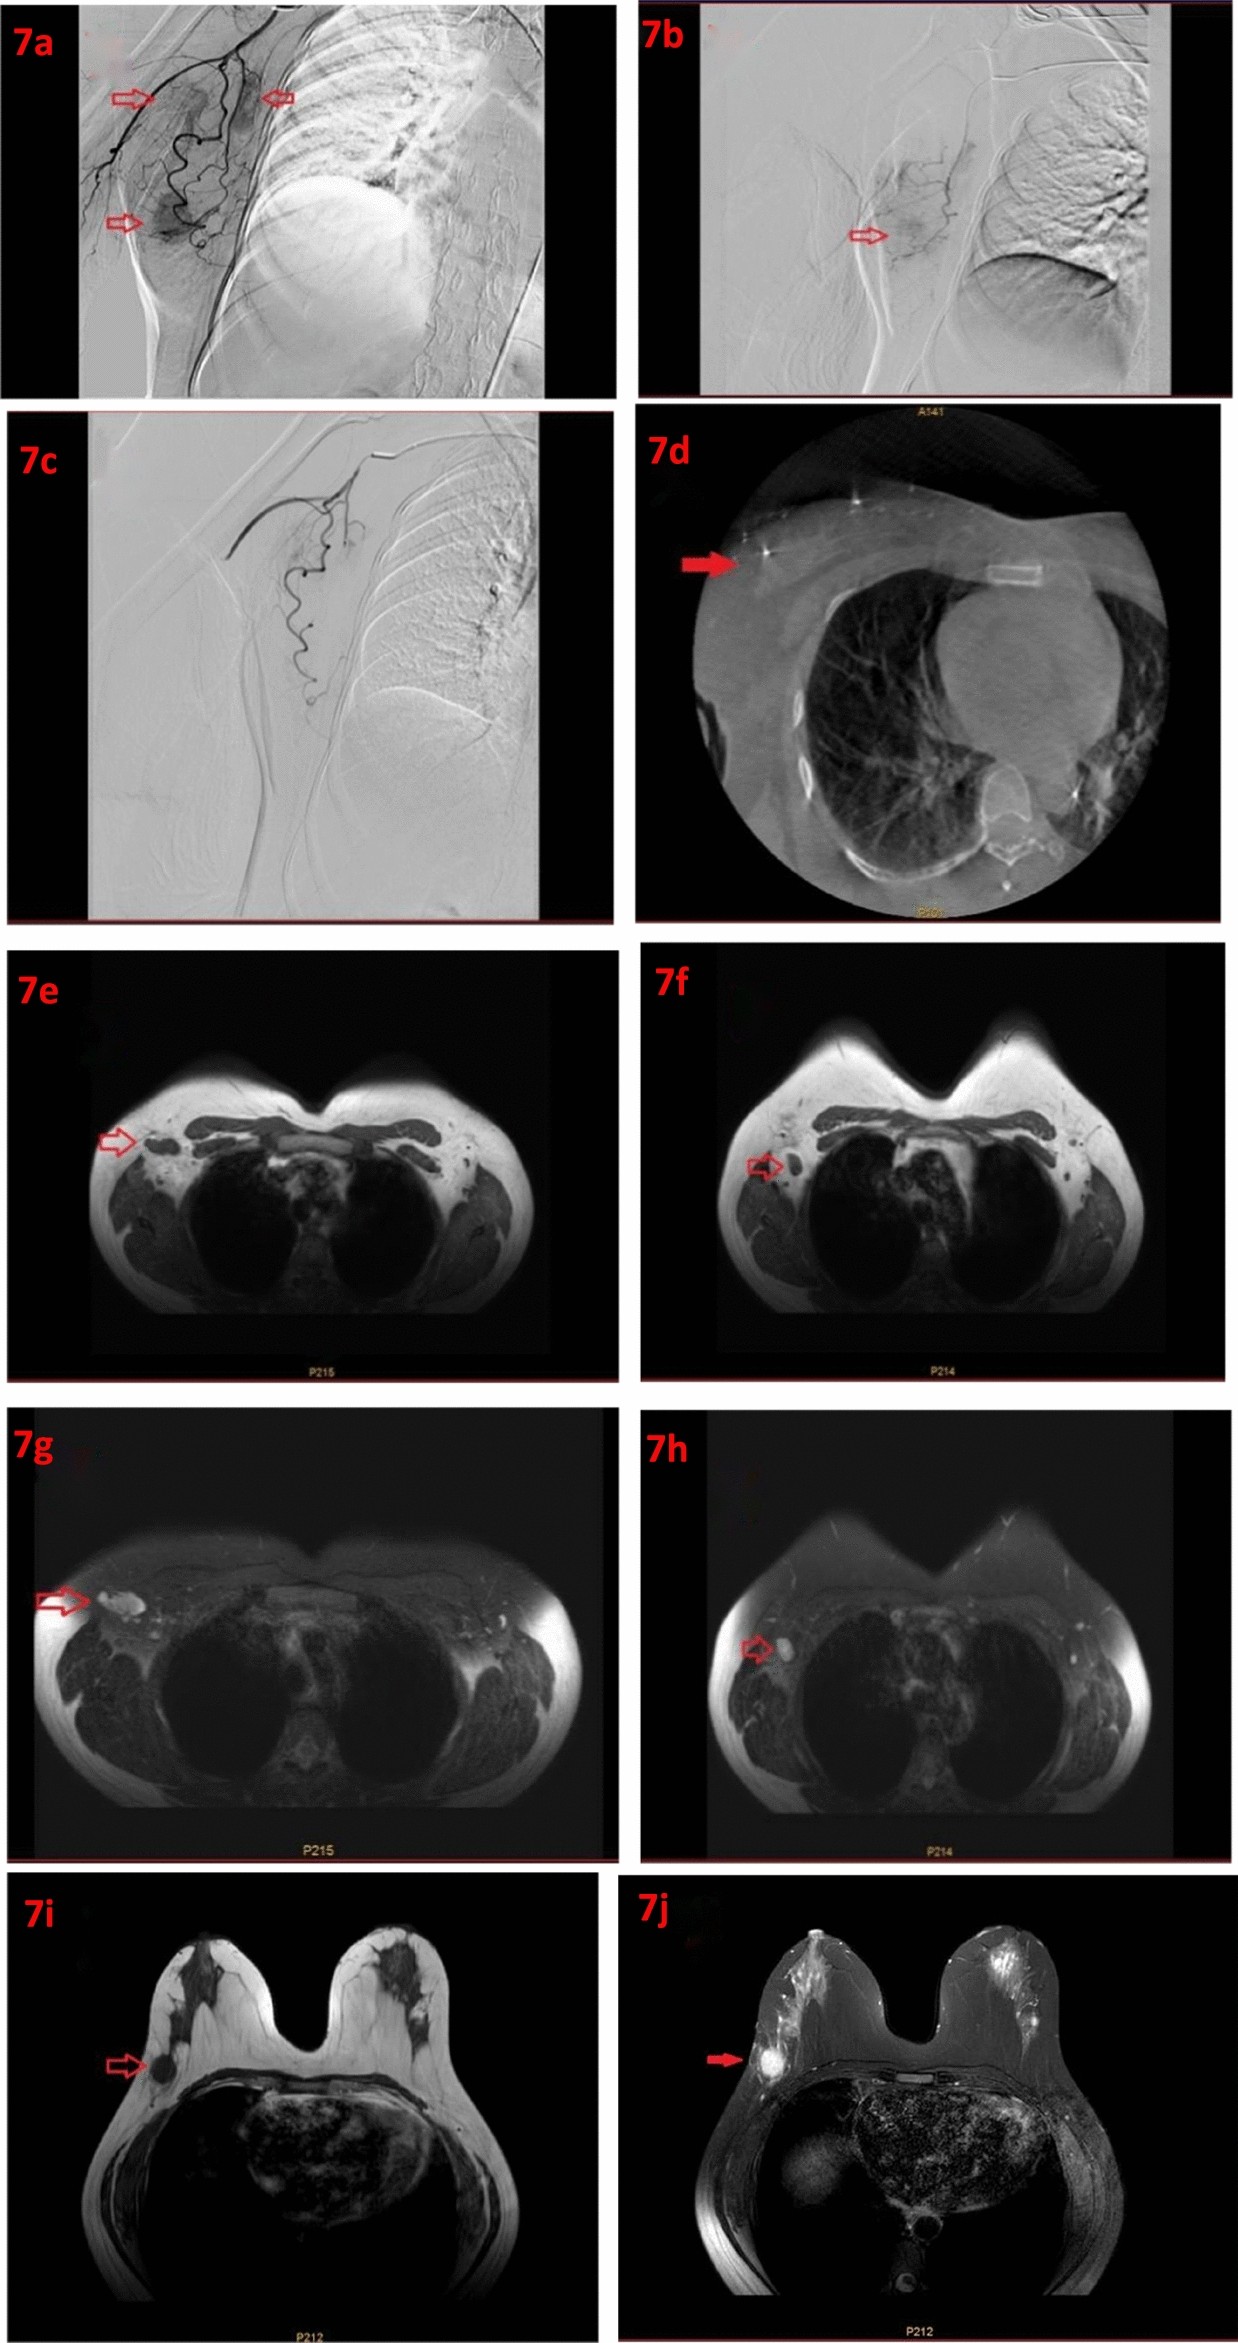

Figure 7

(a) Intraoperative imaging showing breast tumor and axillary lymph node staining. (b) Intraoperative imaging showing breast tumor and axillary lymph node staining. (c) Tumor staining disappeared after embolization. (d) Cone beam computed tomography (CBCT) showing breast tumor staining. (e) T1-weighted imaging of axillary lymph nodes (T1 WI). (f) T2-weighted imaging of axillary lymph nodes (T2 WI). (g) T1-weighted imaging (T1 WI). (h) T2-weighted imaging (T2 WI). (i) Axillary lymph nodes disappeared after treatment. (j) Primary breast lesions disappeared after treatment.